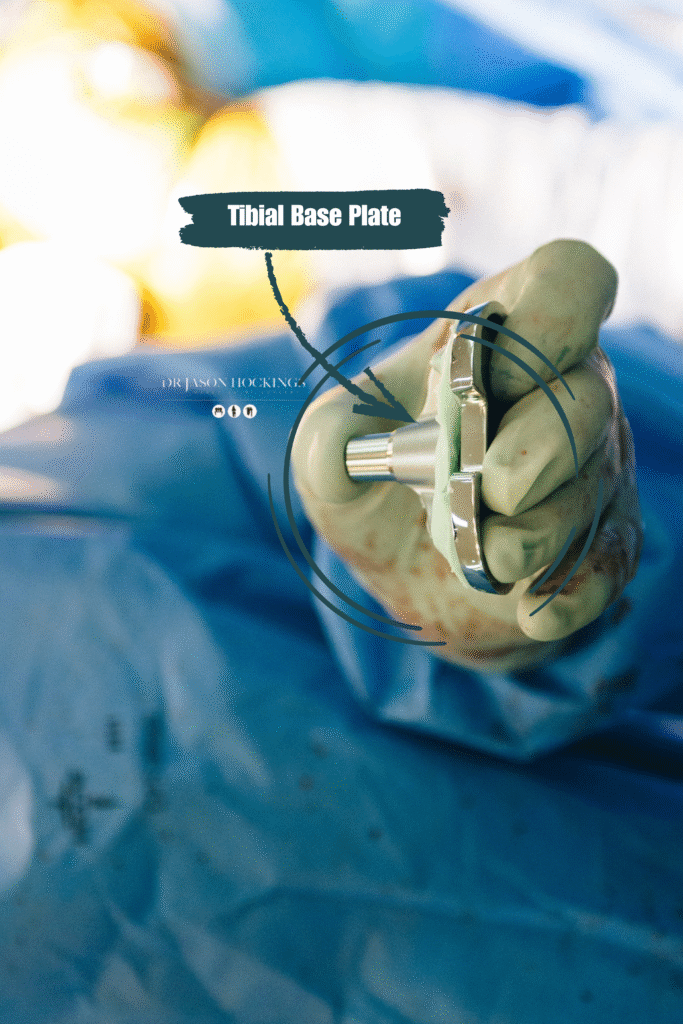

TIBIAL COMPONENT

A metal baseplate that sits on the top of the shin bone (tibia), often with a polyethylene (plastic) insert that serves as the new weight-bearing surface.

- Cobalt-chromium or titanium alloy for the femoral and tibial components, chosen for strength and wear resistance

IMPLANT FIXATION METHODS

Dr Hockings most commonly uses cementless (press-fit) fixation, where the implant is designed to encourage natural bone growth into the surface of the component. This biological fixation method may offer long-term durability and is well-suited to patients with good bone quality. In some cases, cemented fixation may be used, especially if bone quality is lower or if other clinical factors suggest it would be more appropriate. Cemented implants are bonded to the bone using a special surgical cement, allowing immediate fixation.